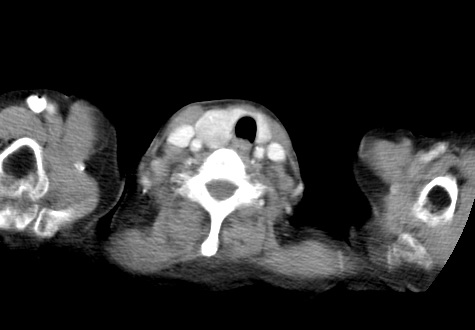

标题: CT23982:女67岁,胸部扫描时发现,甲状腺瘤? [打印本页]

标题: CT23982:女67岁,胸部扫描时发现,甲状腺瘤?

右侧甲状腺腺瘤!支持!不排除甲状腺癌可能!建议手术切除!

右侧甲状腺占位性病变,性质待定(甲状腺腺瘤?);建议:必要时行进一步检查。

右侧甲状腺占位性病变,性质待定(甲状腺腺瘤?);建议穿刺活检。

右侧甲状腺占位性病变,甲状腺腺瘤可能,建议穿刺活检。